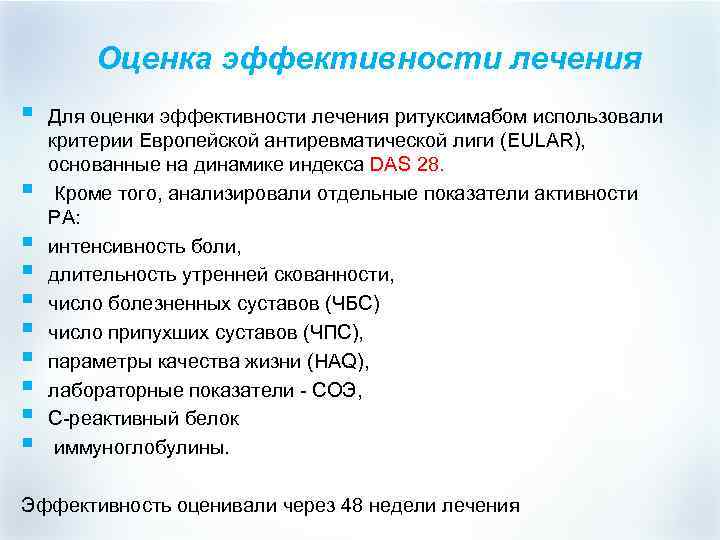

Оценка эффективности лечения § § § § § Для оценки эффективности лечения ритуксимабом использовали критерии Европейской антиревматической лиги (EULAR), основанные на динамике индекса DAS 28. Кроме того, анализировали отдельные показатели активности РА: интенсивность боли, длительность утренней скованности, число болезненных суставов (ЧБС) число припухших суставов (ЧПС), параметры качества жизни (HAQ), лабораторные показатели - СОЭ, С-реактивный белок иммуноглобулины. Эффективность оценивали через 48 недели лечения

Оценка эффективности лечения § § § § § Для оценки эффективности лечения ритуксимабом использовали критерии Европейской антиревматической лиги (EULAR), основанные на динамике индекса DAS 28. Кроме того, анализировали отдельные показатели активности РА: интенсивность боли, длительность утренней скованности, число болезненных суставов (ЧБС) число припухших суставов (ЧПС), параметры качества жизни (HAQ), лабораторные показатели - СОЭ, С-реактивный белок иммуноглобулины. Эффективность оценивали через 48 недели лечения